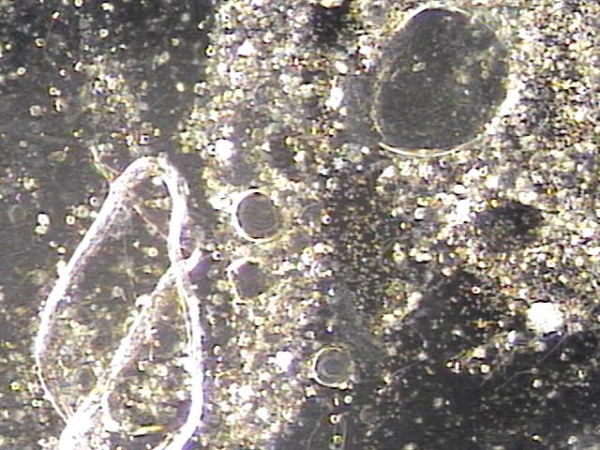

전립선과 정낭과 정관 그리고 사정관 등에서 전립선의 표적 치료후 배양 검사를 하기위해 배출된 결석과 혈정액의 현미경 학적 사진입니다.

Microscopic image of stones and hematospermia discharged from the prostate, seminal vesicles, vas deferens, and ejaculatory ducts following targeted prostate therapy, collected for culture testing.

주2 ~3회 서울가정의학과에서 전립선과 사정관, 정관 그리고 정낭등의 표적 치료후 수명을 다하고 탈락되어 정관과 사정관 그리고 전립선관 등에 막혀 있던 탈락된 상피세포와 치료된 혈정액의 현미경학적 사진입니다.

This is a microscopic image of detached epithelial cell clusters and treated hematospermia that were discharged following targeted treatment of the prostate, ejaculatory duct, vas deferens, and seminal vesicles, performed 2 to 3 times per week at Seoul Family Medicine Clinic. These epithelial cells had reached the end of their life cycle and were obstructing the vas deferens, ejaculatory duct, and prostatic ducts prior to treatment.

전립선과 사정관과 정낭 그리고 정관등이 표적치료를 한다음 배출된 정낭의 결석과 혈정액의 현미경 학적 검사 자료상 머리카락의 굵기와 비교하여 치료를 하므로 열심히 치료하여 건강하게 삶을 삽시다.

This is a microscopic examination of seminal vesicle stones and hematospermia discharged after targeted treatment of the prostate, ejaculatory ducts, seminal vesicles, and vas deferens. By comparing their size to the thickness of a human hair, we can see the importance of precise treatment. Let’s continue treatment diligently and live a healthy life.